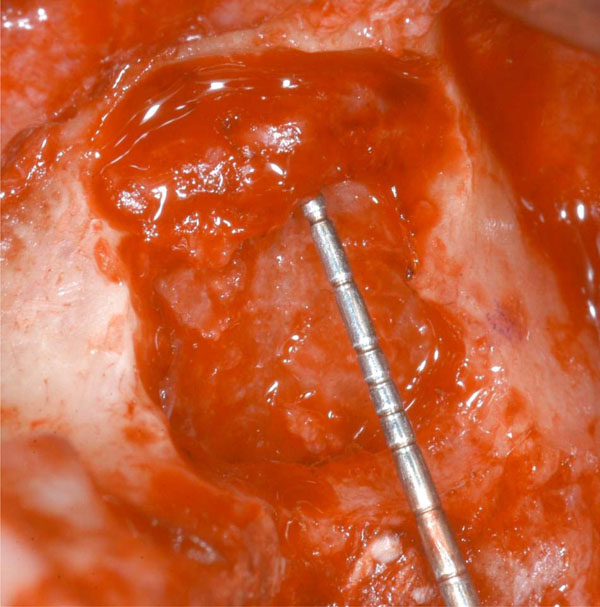

Fig. (9).

(8 and 9). AAA course in two cases in which the double window technique hasn’t been used. As well seen, the artery is exposed and damages can easily occur.